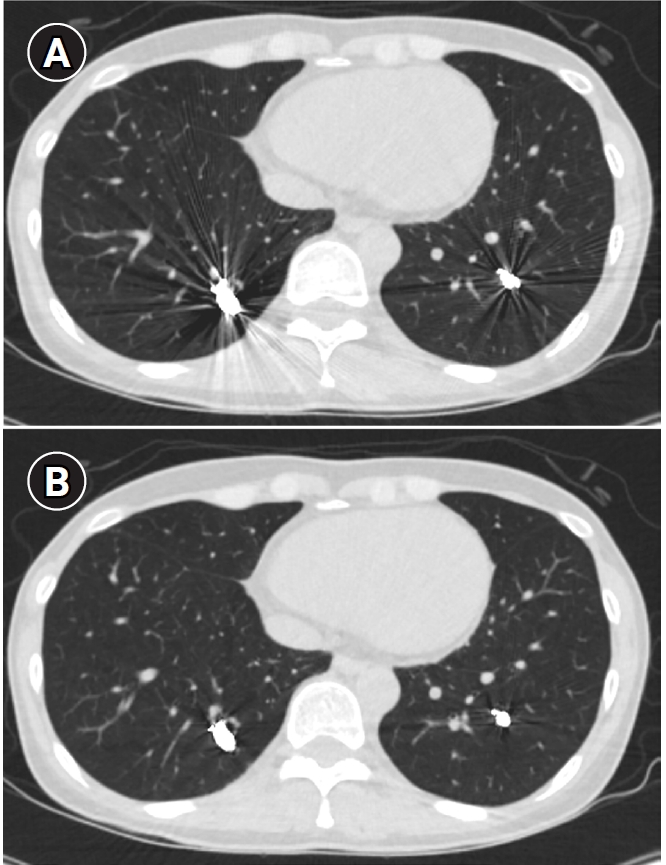

Fig. 9.

Computed tomographic images of a patient with bilateral lower lobe pulmonary arteriovenous malformations treated with coil embolization. (A) Image without metal artifact reduction, showing prominent beam-hardening artifacts that obscure the evaluation of surrounding vessels and parenchyma. (B) Image with metal artifact reduction technique applied, significantly reducing beam-hardening artifacts and allowing for better evaluation of the adjacent vessels and parenchyma.

kjir-2026-00010f9.jpg

Long-term follow-up after treating PAVMs is needed to detect newly developed PAVMs and to identify persistence or recurrent flow [10,11]. Treatment failure in PAVMs can be classified as recanalization and reperfusion. Recanalization refers to the reopening of blood flow through spaces between the previously placed embolic material (Fig. 6). Reperfusion, on the other hand, occurs when blood flow from an adjacent pulmonary artery reopens the previously embolized distal vein or venous sac (Fig. 7) [32]. As the primary follow-up modality, CT is recommended, but there are currently no specific guidelines on whether or not to use contrast enhancement [33]. It is recommended to perform an initial evaluation by CT about 6 months after PAVM embolization, and then follow-up with CT every 3–5 years thereafter (Fig. 8). In CT follow-up, the evaluation is based on the reduction rate of the venous sac or the draining vein, and the traditional criterion is that there should be at least a 70% reduction in the size of the venous sac or draining vein [34,35]. In recent studies, there have been opinions that this 70% size reduction criterion is too strict. In response, some research using angiographic-confirmed cases or time-resolved magnetic resonance angiography (TR-MRA) has proposed a 50%–60% guideline [36,37]. When using CT, repeated radiation exposure and metal artifacts from the coils can be problematic. By using metal artifact reduction techniques, it is possible to obtain clear images of the surrounding parenchyma, and this also helps in assessing parameters like the draining vein diameter reduction rate (Fig. 9) [38]. Furthermore, low-dose CT protocols may help reduce cumulative radiation exposure during repeated follow-up imaging.